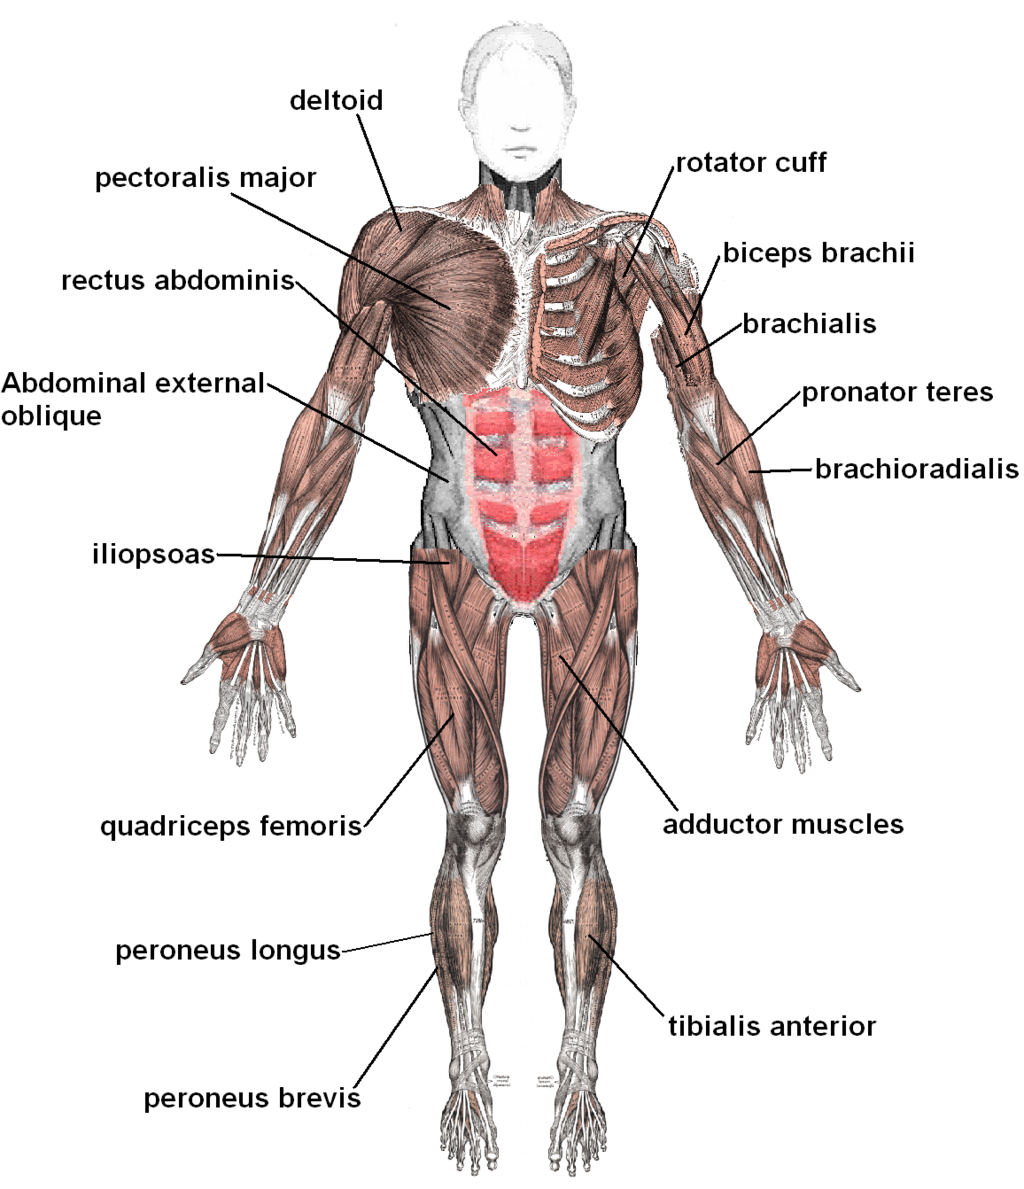

The function of muscles is to tolerate movement of the body. They are made up of small bundles of fascicles or muscle fibers. Fascicles, in turn, are made up of single muscle fibers that are connected to each other in a special way that gives them the capacity to slide simultaneously. The reason why is that muscles can be slid apart, shortened, and permit the muscles to increase in length. Muscles move in harmony with bones with the help of tendons which enable the muscles to attach with the bones. The shifting of the muscles to the tendons happens slowly as tendon fibers give way to muscle fibers prior to the bone attachment. Tendons may vary from short to long depending on their location in the body. The muscles can shorten and pull the tendons as the muscles contract.

A torn muscle is an injury triggered by an overstretched tendon or muscle. The bundle of fiber is torn apart and loses its ability to contract. The amount of tissue damage is the basis for the severity of the injury. The most frequent cause of this condition is overuse of muscles that eventually weaken them. If the joints and muscles perform an activity which they are not designed or prepared to do, an injury can come about from one stressful event, or it may progress slowly after many habitual motions. The damage can be graded on its severity in three areas, such as: the intersection of muscle and tendon, the muscle itself, and the tendon itself.

Pulled muscles are injuries that are caused by damaged ligaments. Ligaments are the thick group of tissues that stabilize and surround joints. This ligament allows the joints to be in motion only on limited directions. A number of joints move about in various planes which, therefore, require more than a group of ligaments to grasp the joint in its proper location and alignment. On each side of the joint, the ligaments are connected to the bone. If a ligament is stretched, then the damage is called a sprain.

The most common location for pulled muscles is the ankles. The mechanism of damage is abruptly twisting or rolling the ankle and rotating it internally so that the foot’s sole starts to point up. This causes damage and stretches the ligaments on the outer part of the ankle. Muscle strains or tears may include any body part that is used to execute work. Back pain in the lower region and spasm is an outcome of frequent lifting injuries.